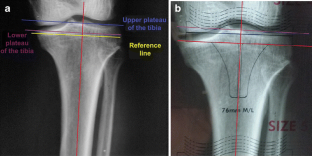

Fig. 3